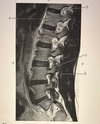

74

1. Thecal sac 2. Cauda equina 3.BaSiveRtebral vein 4. PsOas muscle

1. A)Thecal sac 2. B)Cauda equina 3.C)BaSiveRtebral vein 4. (D)PsOas muscle